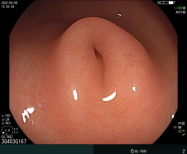

科室高清晰胃肠镜:正常的胃窦(线圈样腺管)和食管粘膜放大观察(IPCL)